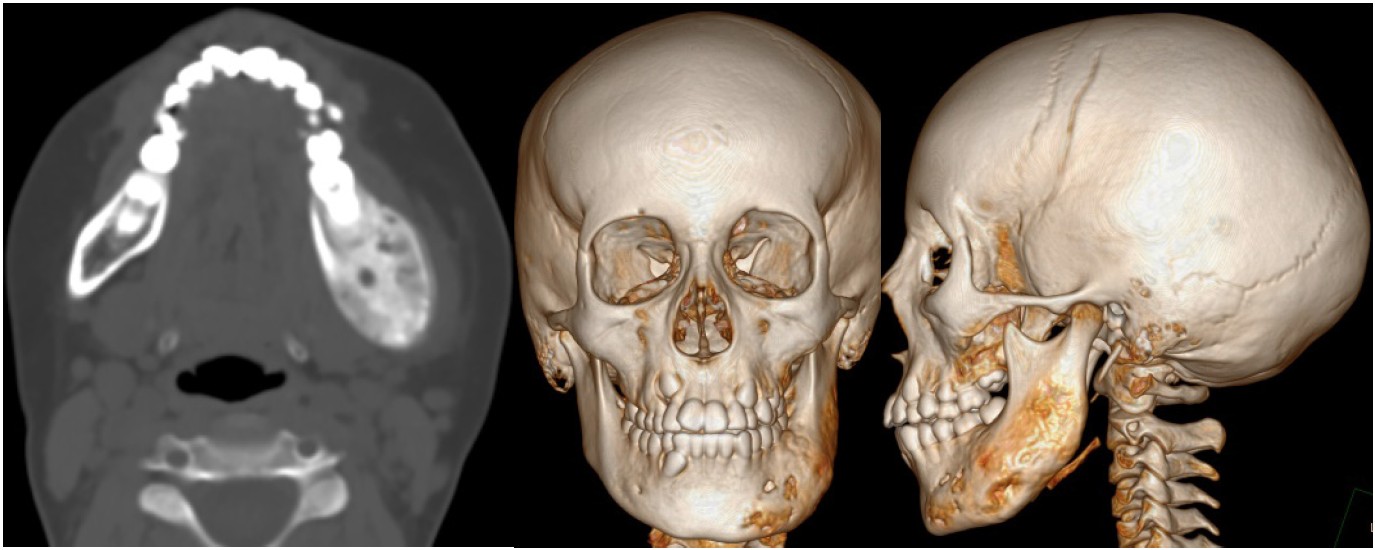

The MSCT imaging reveals edema and deformity in the left segment of the mandible. The affected osseous structure exhibits uneven compaction resembling a «ground glass» appearance, accompanied by localized areas of softening and disruption of the cortical layer. Notably, there is a periosteal thickening along the anterior surface of the altered bone, measuring up to 2.5 mm. Additionally, the mandibular canal demonstrates widening, and the compaction of bone extends into the right segment over a distance of 10 mm. The left masseter muscle appears slightly hypertrophied, and the surrounding soft tissues exhibit edema, with linear compaction extending to the skin (Figure 2).

Fig. 2. MSCT scan in January 2021 shows the affected area that includes the body, angle and the ramus of the left half of the mandible. It can also be noted the widening of the mandibular canal on the left side